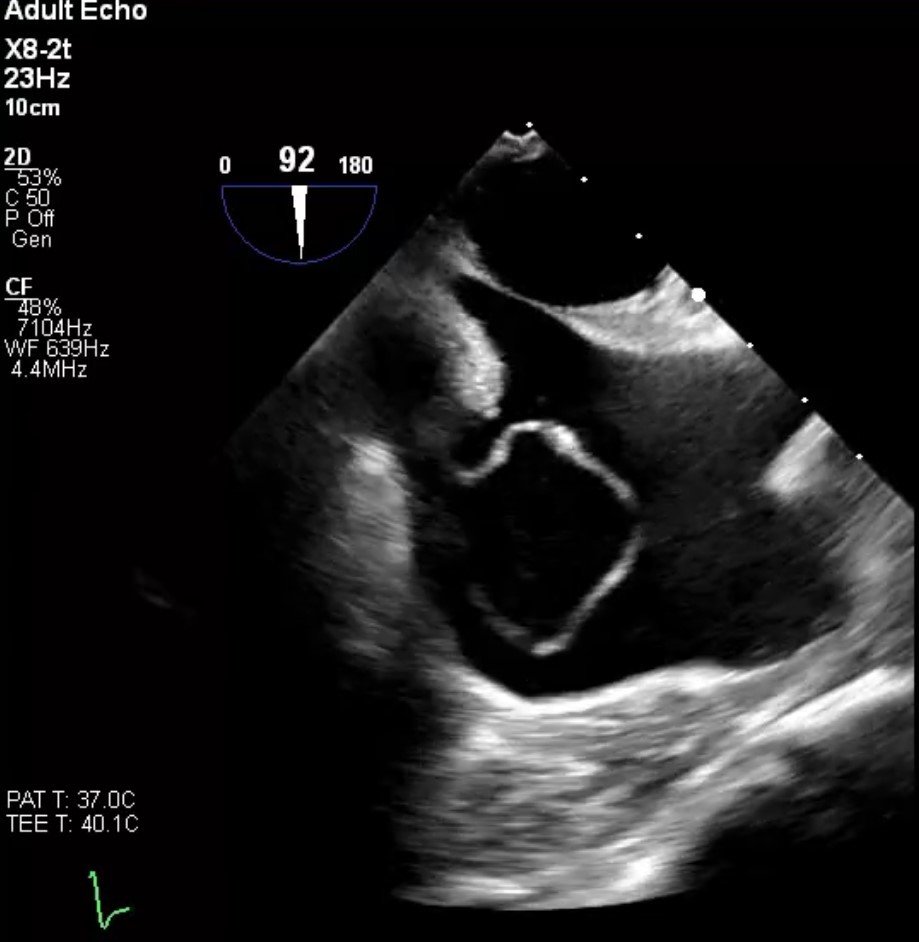

TEE

• Large circular shaped mass that measures approximately 3cm by 2cm that is seen in the right atrium. This mass is "sac -like" in shape.

• Flow is noted in both systole and diastole emptying into the right atrium from at least two distinct areas from this

mass.